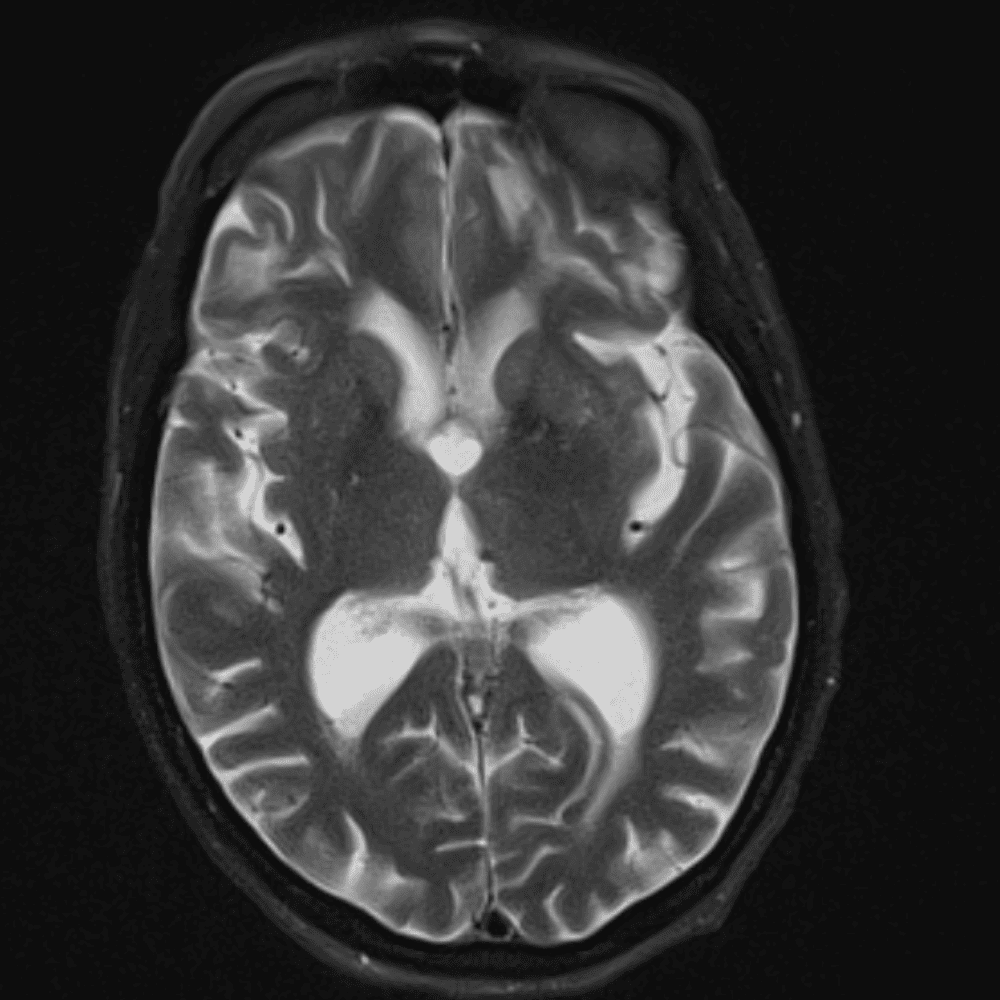

๋‹น์ง ์‹œ ํ”ํžˆ ๋ณผ ์ˆ˜ ์žˆ๋Š” ์‚ฌ๋ก€์˜ ์ „ํ˜•์ ์ธ ์˜ˆ๋ฅผ ํฌํ•จํ•ฉ๋‹ˆ๋‹ค.

39 ์‚ฌ๋ก€